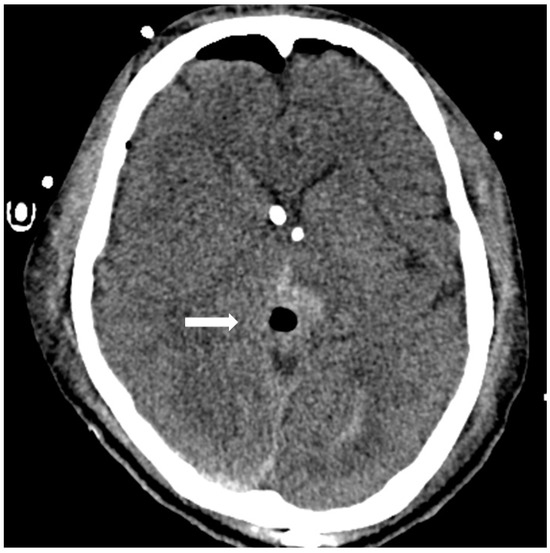

A 24-year-old male, working as a boilerman on a warship, with a hairy body surface, presented to our emergency department with progressively worsening headaches and diplopia for 2 weeks. Initial computed tomography (CT) of the brain revealed a mass with contrast enhancement in the posterior area of the third ventricle. Magnetic resonance imaging (MRI) of the brain revealed a heterogeneously enhancing pineal region mass lesion with obstructive hydrocephalus as shown in Figure 1. Serum samples showed extremely high levels of tumor markers, such as β-HCG and AFP. Surgical intervention with external ventricular drainage was performed as a strategy for CSF diversion, followed by an endoscopy-assisted suboccipital infratentorial approach with the removal of the tumor for cytoreduction, as shown on the brain CT 3 days post-operatively (Figure 2). The frozen section suggested a pineal germinoma, in accordance with its histomorphological pattern. Immunohistochemical staining revealed high expression of glial fibrillary acidic protein, SALL-4 (sal-like protein 4), and placental-like alkaline phosphatase (PLAP) in the pineal tumor, which was confirmed to be a pineal germinoma (Figure 3).

Figure 2.

Postoperative CT showing removal of pineal tumor via an endoscopy-assisted occipital transtentorial corridor and retention of a bilateral external ventricular drainage tube.